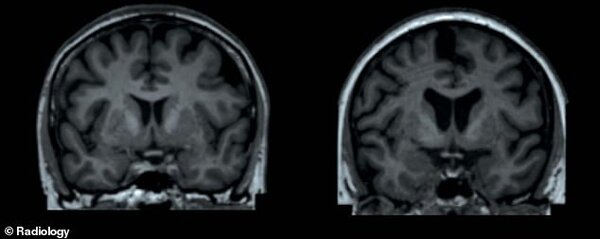

На изображении представлено наглядное сравнение: слева — МРТ мозга женщины с нормальным весом, справа — женщины с избыточной массой тела. Фото: dailymail.co.uk

На этом снимке представлено сравнение МРТ двух женщин одного возраста (65 лет). Слева — мозг женщины с содержанием жира 13%, справа — с содержанием жира 49%. Исследователи отмечают, что на правом снимке визуально заметно уменьшение объемов подкорковых структур серого вещества. Фото: dailymail.co.uk